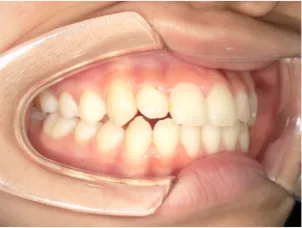

治療中⑦中3:15y5m 口元・咬合の改善で抜歯治療スタート

| 行ったご提案・診断内容 | 成長期に行う治療と咬合治療をご提案 咬合治療でOPEにならないように、成長期に受け口の悪化予防を行い、咬合治療で歯並びと口元の改善を行うことを提案しました。 《成長期治療:成長時期にお口の環境を整え、適正な成長を誘導する治療》 使用装置 《咬合治療:成長期治療後に大人の歯を咬ませる治療》 *治療は上記ステップで行いました。 《治療後の経過観察》 |